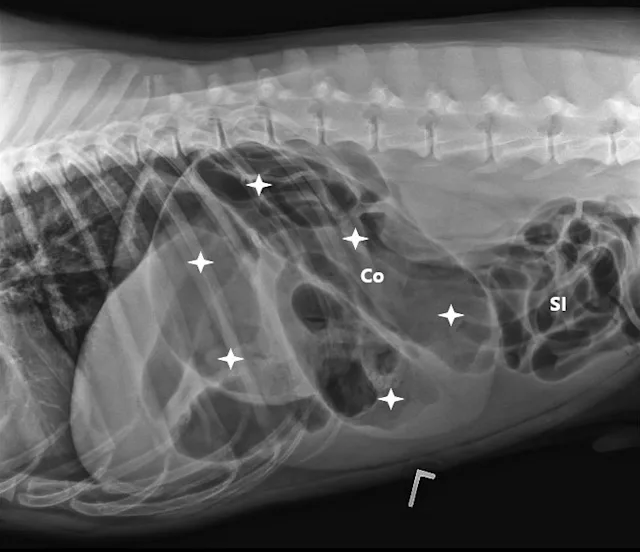

A lubricated 10 French red rubber catheter was inserted rectally and connected to a 60-mL catheter-tip syringe. Air (2 mL/kg) was injected while the anus was occluded by pinching off the anal tissue. Additional 3-view abdominal radiographs revealed normal-diameter, gas-filled small intestines; a markedly gas-distended proximal colon; soft-tissue opacity abnormally located in the right cranial abdomen; and narrowing of the distal lumen of the descending colon (Figure 2). The remainder of the radiographs were unremarkable. Radiographs were assessed by multiple board-certified radiologists, and there was a high index of suspicion for colonic torsion.

FIGURE 1A

Right lateral (A), left lateral (B), and ventrodorsal (C) abdominal radiographs demonstrating marked dilation of a single bowel loop with gas and amorphous material in the right cranial abdomen, suspected to be the colon (arrows). Caudal displacement of the small intestines (SI) can also be seen. The descending colon (Co) is poorly visualized.